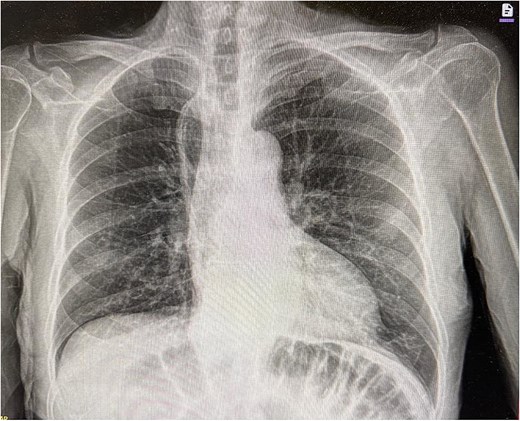

Upon arrival at the ED, the patient was afebrile and hemodynamically stable. Initial labs showed WBC 10.19, H/H 13.2/41.3, platelets 419, Na 136, K 5.3, creatinine 1.0. Portable X-ray and computed tomography (CT) imaging revealed small bowel obstruction secondary to herniation of the small bowel into the right hemithorax through a recurrent hiatal hernia (Figs 1 and 2).

Preoperative CT image showing recurrent hiatal hernia with dilated small bowel in the right hemithorax, mesenteric edema, and surrounding fluid.